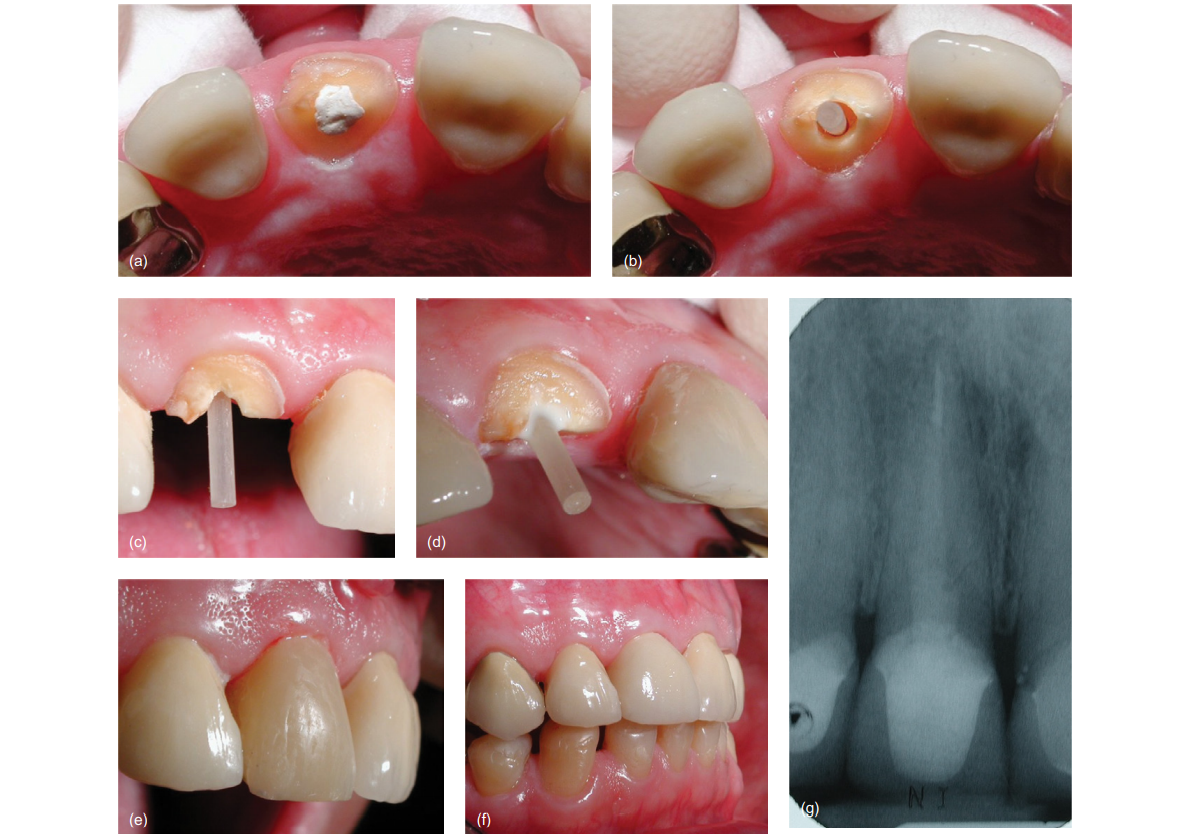

BDS ,MDS (Conservative Dentistry and Endodontics)

Dr. Ananya graduated from the prestigious Manipal College of Dental Sciences, Manipal with a BDS degree and completed her postgraduation (MDS) in Conservative Dentistry and Endodontics from IDS, Bareilly. She has been passionately practicing dentistry since then. With the desire to pursue both academics and also run a clinical practice she continues to serve as a teaching faculty at a dental college in Lucknow and manages her clinic in the evening. Her meticulous approach, experience and desire to provide the best treatment has always enabled her to save teeth in a relatively painless manner. She is also a member of